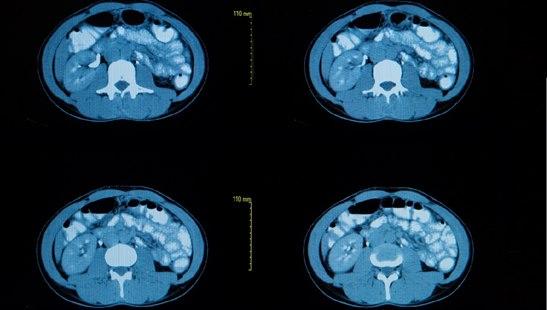

CT av hjertets koronararterier, CT-koronarangiografi, forutsetter bruk av såkalt "multislice"-CT (MSCT), også kalt multidetektor CT-skanner (MDCT) eller ultrarask CT. Ved hjelp av "multislice"-CT kan skanningen utføres mye raskere og med svært tynne snitt, noe som er en forutsetning for å kunne avbilde koronararteriene.

Avansert data-programvare gjør det mulig å fremstille gode bilder med denne teknologien. Foruten å fremstille hulrommet i arteriene, så gir CT-koronarangiografi også opplysninger om karveggen og eventuelle avleiringer, plakk. Undersøkelsen gjør det også mulig å beregne hjertets pumpeevne.